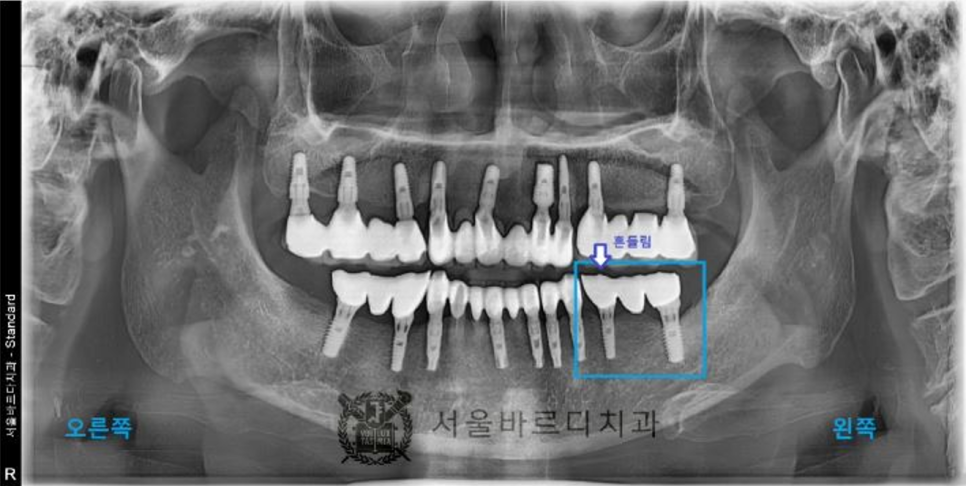

왼쪽 아래 부분의 임플란트 브릿지는 많이 흔들려서

음식을 드실 수 없는 상태이셨습니다.

왼쪽 아래 임플란트는 임플란트와

보철물(크라운)을 연결해주는 나사(스크류)가 헐거워져서

보철물이 흔들리는 것이었습니다.

이런 경우 임플란트 뿌리 부분은 그대로 사사용하고

보철물을 고정시켜주는 나사만 교체하면 됩니다.

하지만 20년 전에 타치과에서 치료하신 임플란트라서

어느 브랜드의 임플란트인지

환자분께서 기억하지 못하셨습니다.